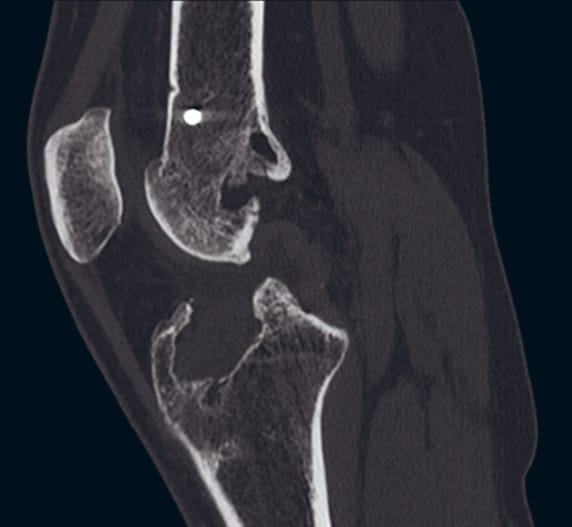

A two-stage reconstruction was indicated, given the patient’s severe tibial tunnel expansion to 23mm. For the ACL, a contralateral patellar tendon autograft was recommended. For the first stage of the two-stage reconstruction, bone grafting with allograft as well as hardware removal for the metal femoral screw was recommended. The second stage would be a contralateral patellar tendon autograft reconstruction with lateral extra-articular iliotibial (ITB) band tenodesis.

Six months after the tibial tunnel bone grafting, there was still a very large tibial defect. Rather than performing a repeat tibia bone graft, we elected to use a laterally-based tibial tunnel. The tunnel was created just adjacent to the tibial tubercle to go on the lateral side and was drilled through entirely virgin bone.